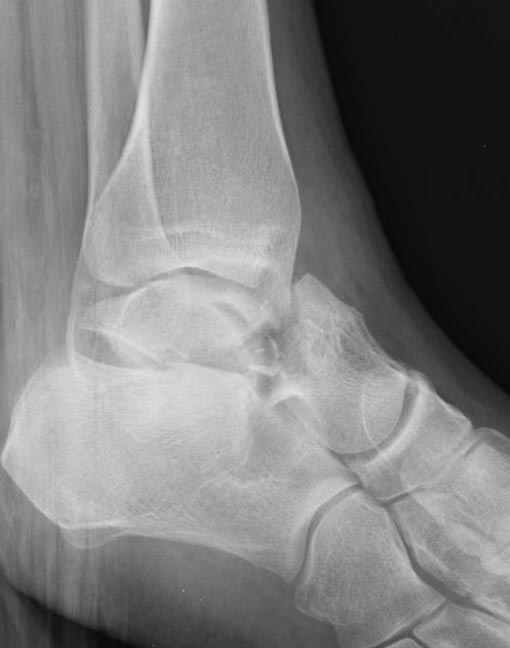

Вдогонку по поводу перелома таранной кости, больная 81, не страдает диабетом, перелом закрытый, в первый же день поступления ограничились временным наружным фиксатором (как на снимке).

Из-за отека на стопе тактика лечения у всех была

одинаковая: временная наружная фиксация до спадения отека, при изолированных переломах они выписывались домой и через дней 7 госпитализировались на оперативное лечение.

Примеры на снимке...